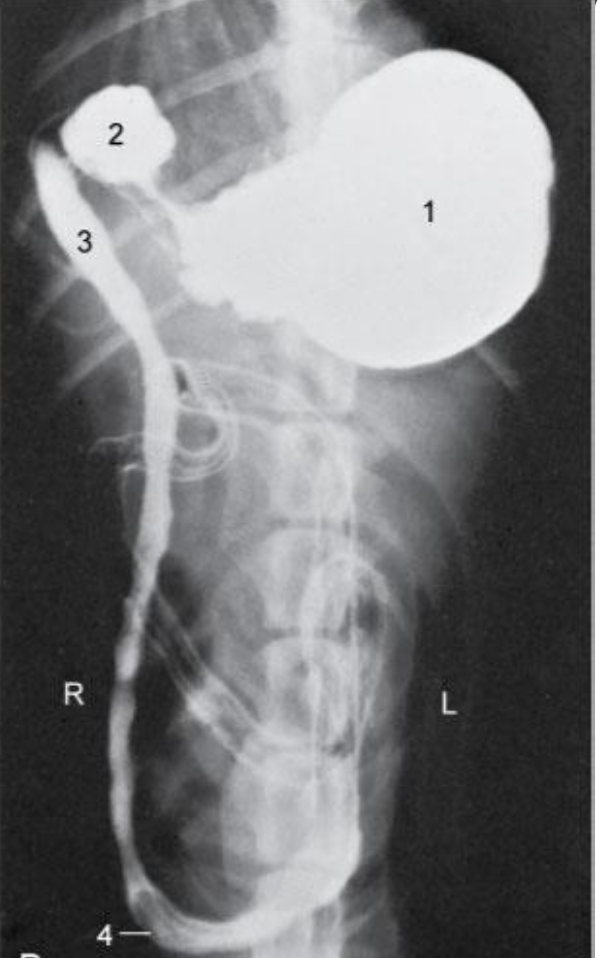

Re. duodenum, topographic position?

Upper right half of the hypochondriac region - 9th intercostal space

Runs caudally (right side) – Descending duodenum- level of tuber coxae- makes a U- turn –runs obliquely-craniosinistrally (leftside)- continues as the ascending duodenum

Re. Cranial duodenum, topographical position?

Dorsally and laterally lies in contact with the liver and medially by the pancreas